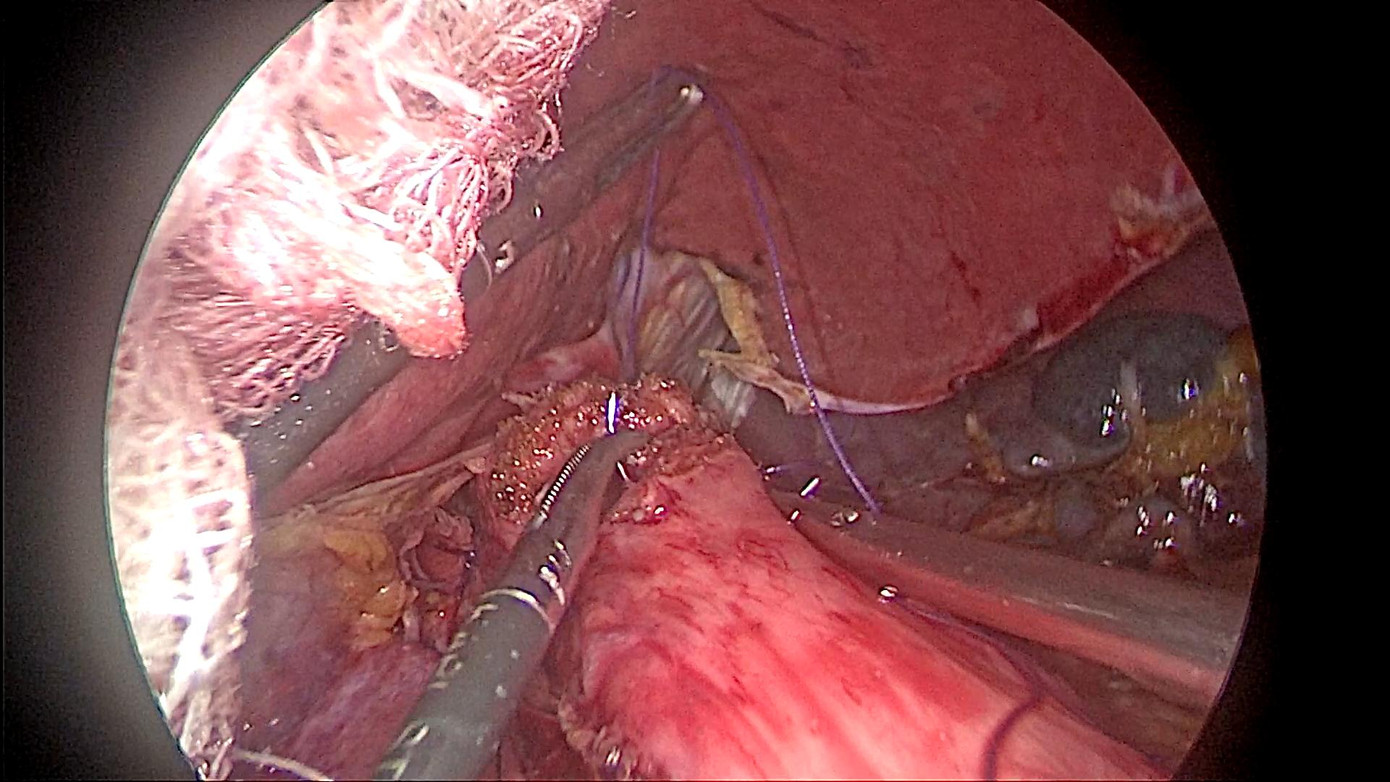

| Phẫu thuật nội soi hoàn toàn cắt cực trên dạ dày, miệng nối thực quản - dạ dày được thực hiện bằng tay (BN Hoàng Thị K) |

Tuy nhiên, khi xin ý kiến mẹ mình, thì bà K lại bảo: Mẹ xem tivi, nghe đài, đọc báo nhiều nên biết Bệnh viện Bạch Mai đang áp dụng nhiều kĩ thuật tiên tiến trong phẫu thuật và đã cứu sống được rất nhiều người mắc bệnh hiểm nghèo. Thể theo nguyện vọng của mẹ, ông Ngô Thanh S (con trai bệnh nhân) đã đưa mẹ đến khám tại Trung tâm Tiêu hóa - Gan mật, Bệnh viện Bạch Mai. Sau khi nội soi, chụp chiếu và làm các xét nghiệm cận lâm sàng cần thiết, bà được chuyển sang Khoa Phẫu thuật Tiêu hóa - Gan mật tụy. Tại đây, các bác sĩ nhận định bệnh nhân K có chỉ định phẫu thuật nội soi cắt đoạn dạ dày, nạo vét hạch. Với sự giúp sức của Trung tâm Gây mê và Hồi sức ngoại khoa, qua 5 lỗ nhỏ trên thành bụng, kích thước từ 0,5 đến 1 cm, các phẫu thuật viên của Khoa phẫu thuật Tiêu hóa - Gan mật tụy đã đưa camera và các dụng cụ nội soi tiếp cận, phẫu tích, bóc tách dạ dày và các mạch máu, hạch liên quan.

Sau khi đoạn dạ dày bị ung thư cùng mạc nối, hạch được cắt đi cả khối, mỏm dạ dày được nối với hỗng tràng cũng qua nội soi. Ca mổ kéo dài trong khoảng 3 tiếng và thành công đúng như dự kiến. Chỉ 2 ngày sau phẫu thuật, bà K đã có thể ăn cháo và đi lại nhẹ nhàng. Điều khiến gia đình bà K vô cùng bất ngờ là chỉ sau 5 ngày, sức khỏe của bà K khôi phục gần như bình thường. “Tôi cũng rất ngạc nhiên, mẹ tôi đã 91 tuổi lại trải qua một cuộc đại phẫu như vậy, nhưng nhờ áp dụng phương pháp phẫu thuật tiên tiến mà mẹ tôi phục hồi rất nhanh. Tôi thực sự rất biết ơn các y, bác sĩ và nhân viên tại Khoa Phẫu thuật Tiêu hóa - Gan mật tụy”. Đó là lời cảm ơn của con trai bà K gửi tới bác sĩ trước khi mẹ mình xuất viện.